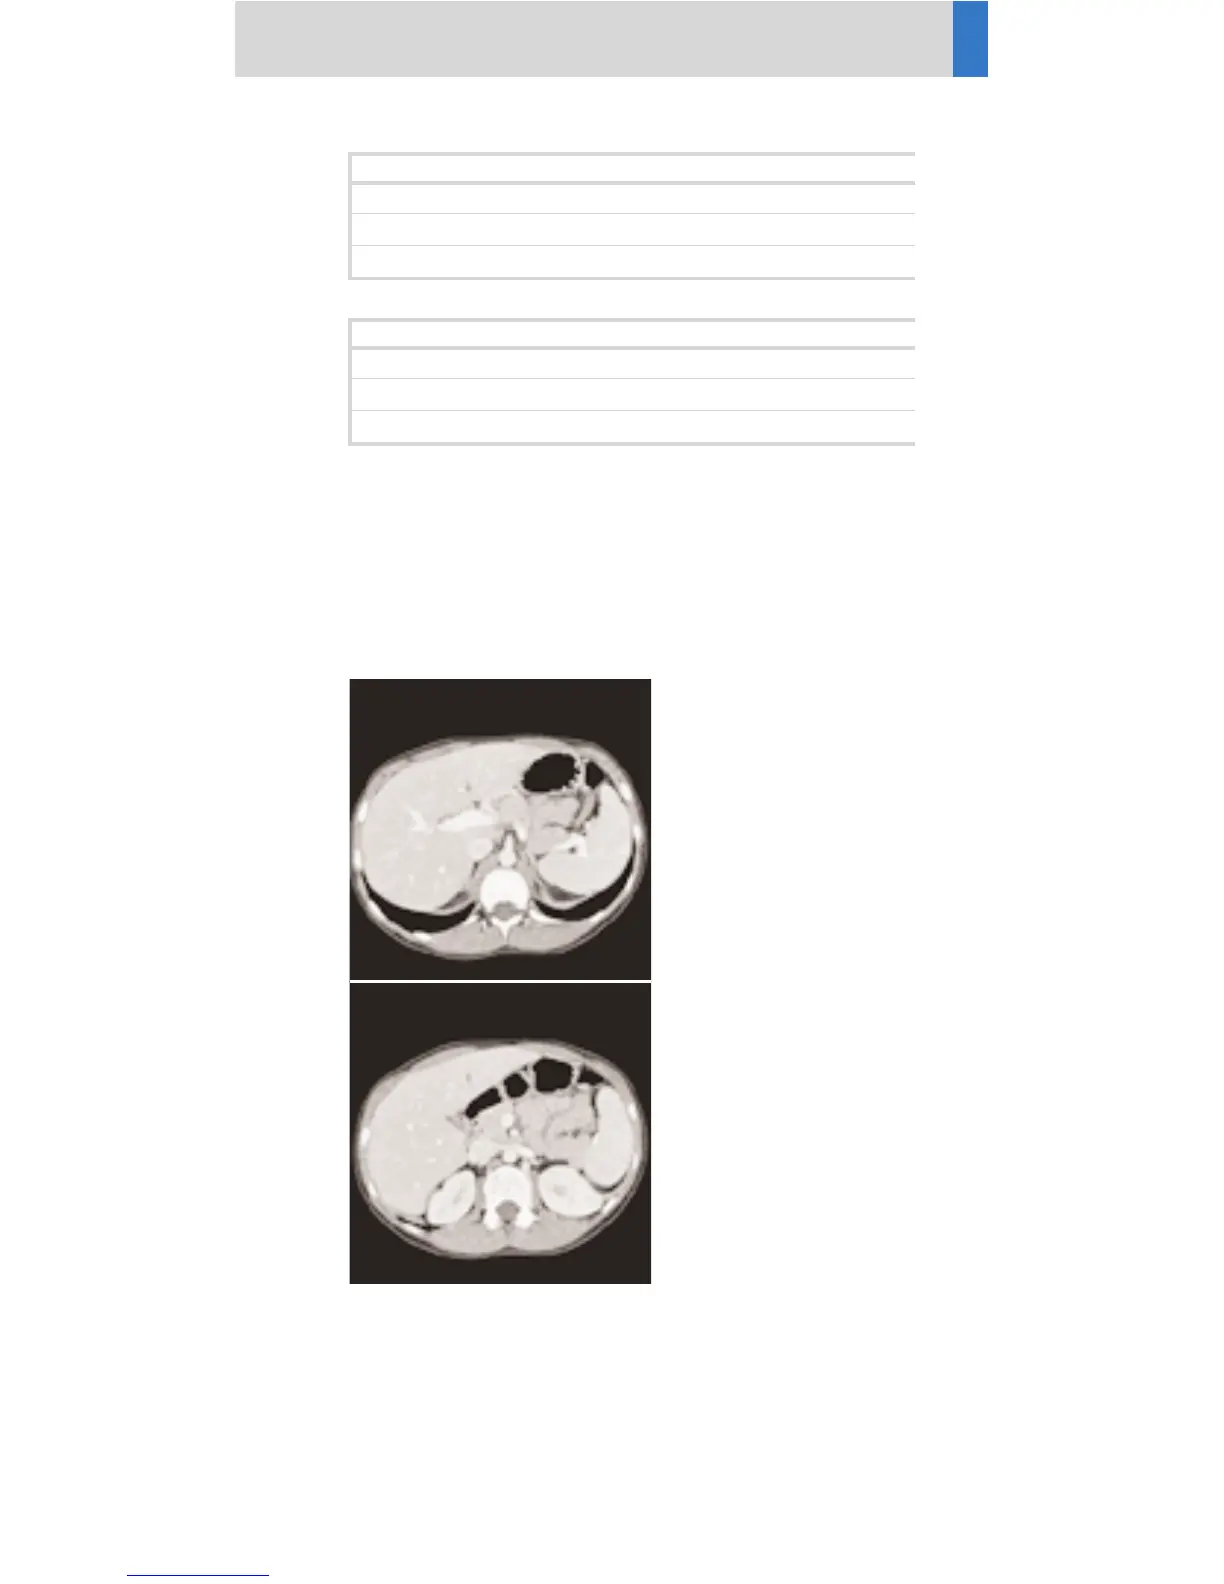

MIPthin: AbdCTA sagittal

Image thickness 3

Distance between images 3

Number of images 60